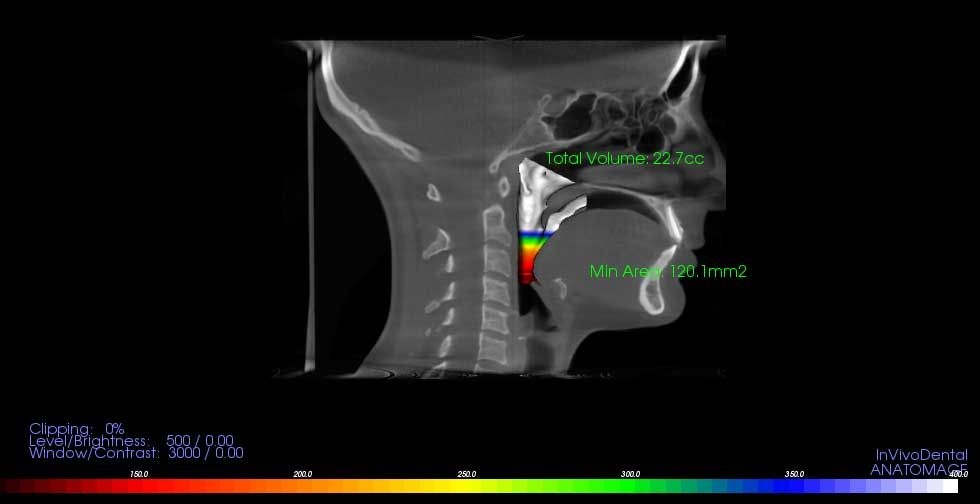

3D-диагностика челюстно-лицевой области на KaVo 3D eXam

KaVo 3D eXam — высокоточная 3D-визуализация

Наш томограф KaVo 3D eXam обеспечивает:

• быстрое сканирование (обычно несколько секунд) и мгновенную визуализацию на мониторе — это удобно для пациента и ускоряет процесс диагностики;

• широкий диапазон полей обзора — от одного зуба до всей челюстно-лицевой области;

• высокое разрешение и точность, необходимые для решения задач в имплантологии, ортодонтии, эндодонтии и диагностике ВНЧС;

• сниженные дозовые нагрузки по сравнению с традиционными спиральными КТ головы и шеи;

• комфорт и стабильность при позиционировании: открытая конструкция и удобное сидячее положение пациента.